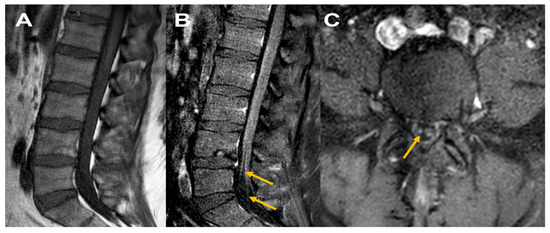

A 41-year-old male presented to the ED post-COVID-19 vaccination (Johnson & Johnson vaccine) with complaints of generalized weakness, difficulty ambulating two weeks post-vaccination. On physical examination MRC grade 4/5 in lower extremity throughout. Reflexes were absent. Upon admission, MRI of the brain, lumbar spine, and cervical spine without contrast were unremarkable. CSF revealed increased protein, normal cell count, and albumino cytological dissociation. EMG/NCS revealed findings consistent with demyelinating polyneuropathy. The patient was treated with and responded well to IVIG. At a two-month follow-up, the patient stated he was ambulating with assistance. Follow-up lumbosacral spinal MRI imaging with/without contrast revealed thickened cauda equina nerves. These findings raised concern for disease progression to chronic inflammatory demyelinating polyneuropathy (CIDP) (Figure 2).

Figure 2. MRI Lumbar spine Figure 2, sagittal T1 plain (A) and corresponding sagittal post contrast T1 (B) and axial cuts at L5 level (C) reveal normal appearing disc and facets, Figure 1A; cauda equina nerve roots are thickened with no abnormal enhancement consistent with chronic inflammatory demyelinating polyneuropathy (B) and (C).